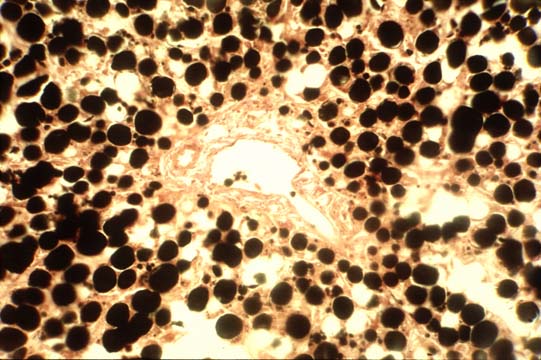

CELLULAR CHANGES: Steatosis

The liver is involved in lipid metabolism but normally only 5% of its weight is due to fat and fat is not seen in normal liver.. Fat storage will however increase and become visible under conditions which will affect various steps of fat metabolism,either in the uptake of dietary fat as in obesity,or in the mobilization of fatty deposits as in acute illnesses,or in the synthesis and degradation of fatty acids,tiglycerides,cholesterol and lipoproteins,or, finally in the secretion and export of synthesized fats. The stored fat consists mostly of triglycerides and therefore can be demonstrated with stains for fats such as oil red O,sudan IV,etc.,but the most recomandable,in my opinion,is osmium teroxide especially for microvesicular fat and for needle biopsies when the tissue cannot be wasted.

Fig 36 - Fat in macrovesicles

peripheral nuclei,

no cellular damage